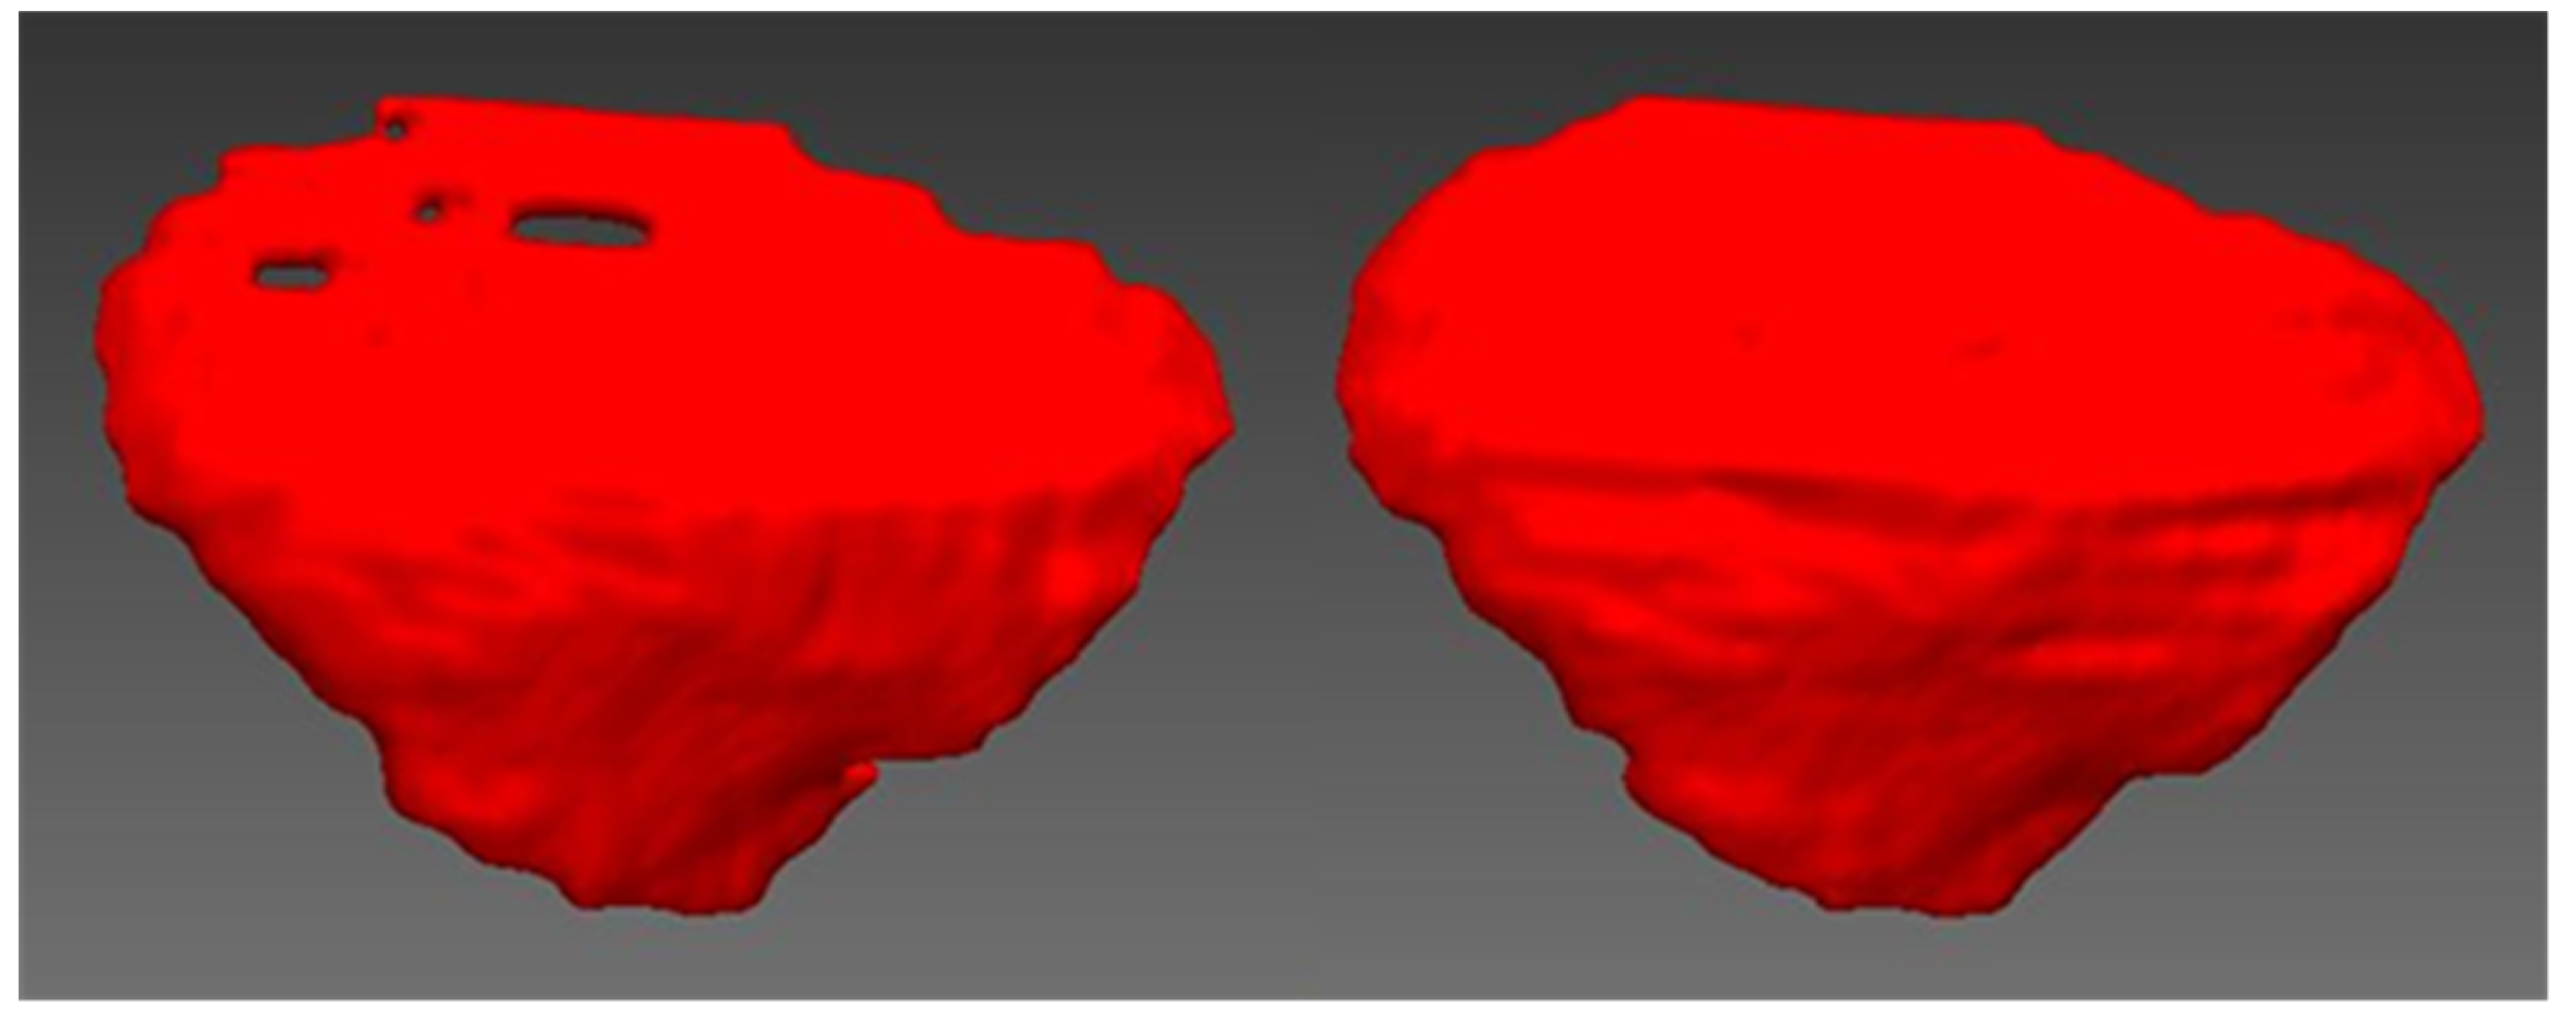

When every fifth slice interpolation method was performed, the slices involved were 91, 96, 101, 106, 111, 116, 121, 126, 131, 136, 141, 146, 151, 156, 161, 166, 171, 176, 181, 186, 191, 196, 201, 206, 211, 216, and 221. The total number of slices was 27. The result of the patient-specific cranial implant using the shape-based interpolation method on every tenth slice and fifth slice were saved in STL format and exported to STL format, as shown in Figure 8.

Figure 8.

The patient-specific cranial implant with every tenth slice interpolation (left) and every fifth slice interpolation (right).